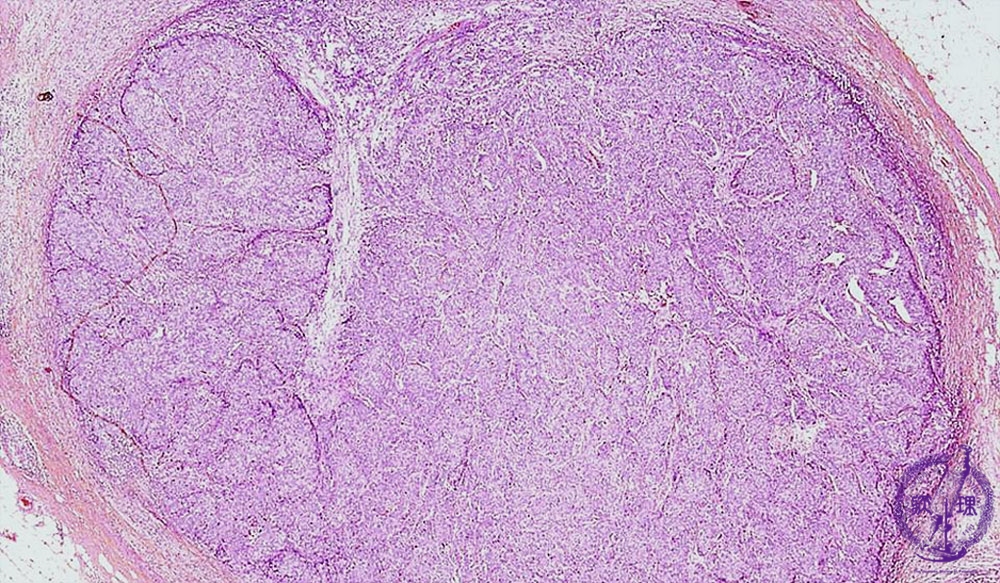

• š(6)Invasive ductal carcinoma(Solid-tubular carcinoma)

Microscopic image(HE stain, low power view):Solid carcinoma cell nests are highly proliferative. Middle sized nests result in a lobulated appearance. An expansive growth of carcinoma cells can also be appreciated at the margin of the tumor.